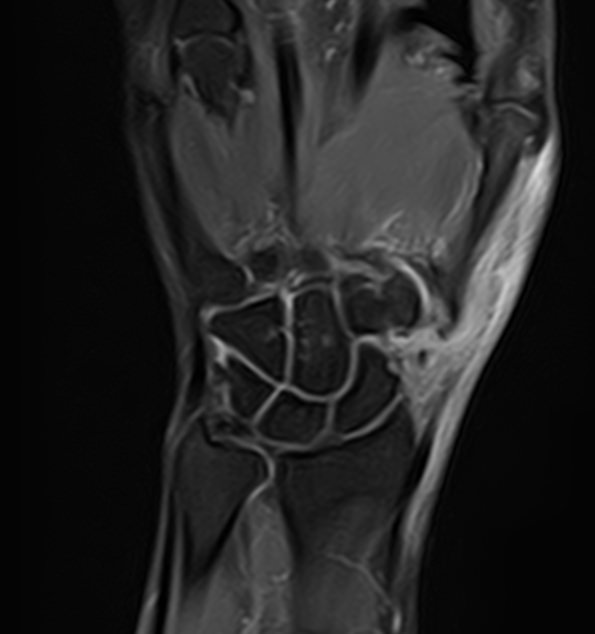

Магнитно-резонансная томография является современным высокоточным методом диагностики заболеваний опорно-двигательной системы человека. Во время исследования аппарат послойно сканирует анатомическую зону в различных плоскостях, затем с помощью компьютерных программ формирует трехмерные изображения с высокой точностью и достоверностью, что позволяет проводить эффективную диагностику заболеваний суставов.

Для выявления причин множественного поражения суставов в клинике «Доступная медицина» проводится комплексное обследование МРТ двух суставов, включающее два протокола исследования каждой анатомической области. При одностороннем поражении сустава также может назначаться МР сканирование одновременно двух симметричных сочленений для сравнения пораженной области со здоровым суставом на противоположной стороне. Это позволяет проводить более эффективную диагностику заболеваний суставов и назначать успешное лечение.

Какую патологию суставов можно выявить с помощью МРТ

• Из-за интенсивных нагрузок суставы часто подвержены травматизации (вывихи, подвывихи, внутрисуставные переломы, кровоизлияния в полости суставов – гемартрозы, растяжения, разрывы связок и сухожилий, ушибы мягких тканей),

• Воспалительные заболевания суставов (артриты, бурситы, синовиты, тендиниты, тендовагиниты).

• Дегенеративно-дистрофические заболевания суставов (артрозы, остеоартрозы).

• Врожденные аномалии развития (дисплазии, различные деформации и др).

• Выявление доброкачественных новообразований, например, кист и злокачественных опухолей (как первичных, так и метастазов).

• Обнаружение сосудистых заболеваний, поражений нервных волокон, патологии окружающих сустав мягких тканей.